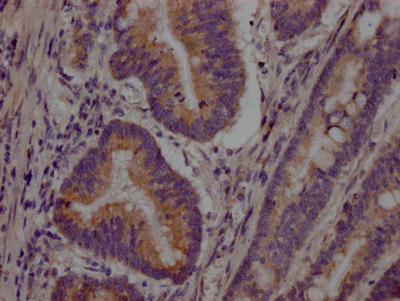

CSB-RA259644A0HU IHC

Tested Applications:

ELISA, WB, IHC